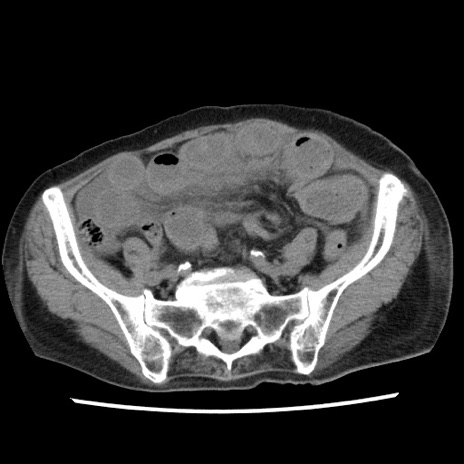

症例1(横断像)

症例

【症例】80歳代女性

【主訴】腹痛

【現病歴】8時間前から腹痛あり来院。

【既往歴】糖尿病、脂質異常症、子宮体癌にて子宮全摘術

【身体所見】意識清明・会話良好だが腹痛で苦悶様、全腹部にわたって反跳痛と圧痛あり

【データ】WBC 13600、CRP 0.14、LDH 224、CK 90